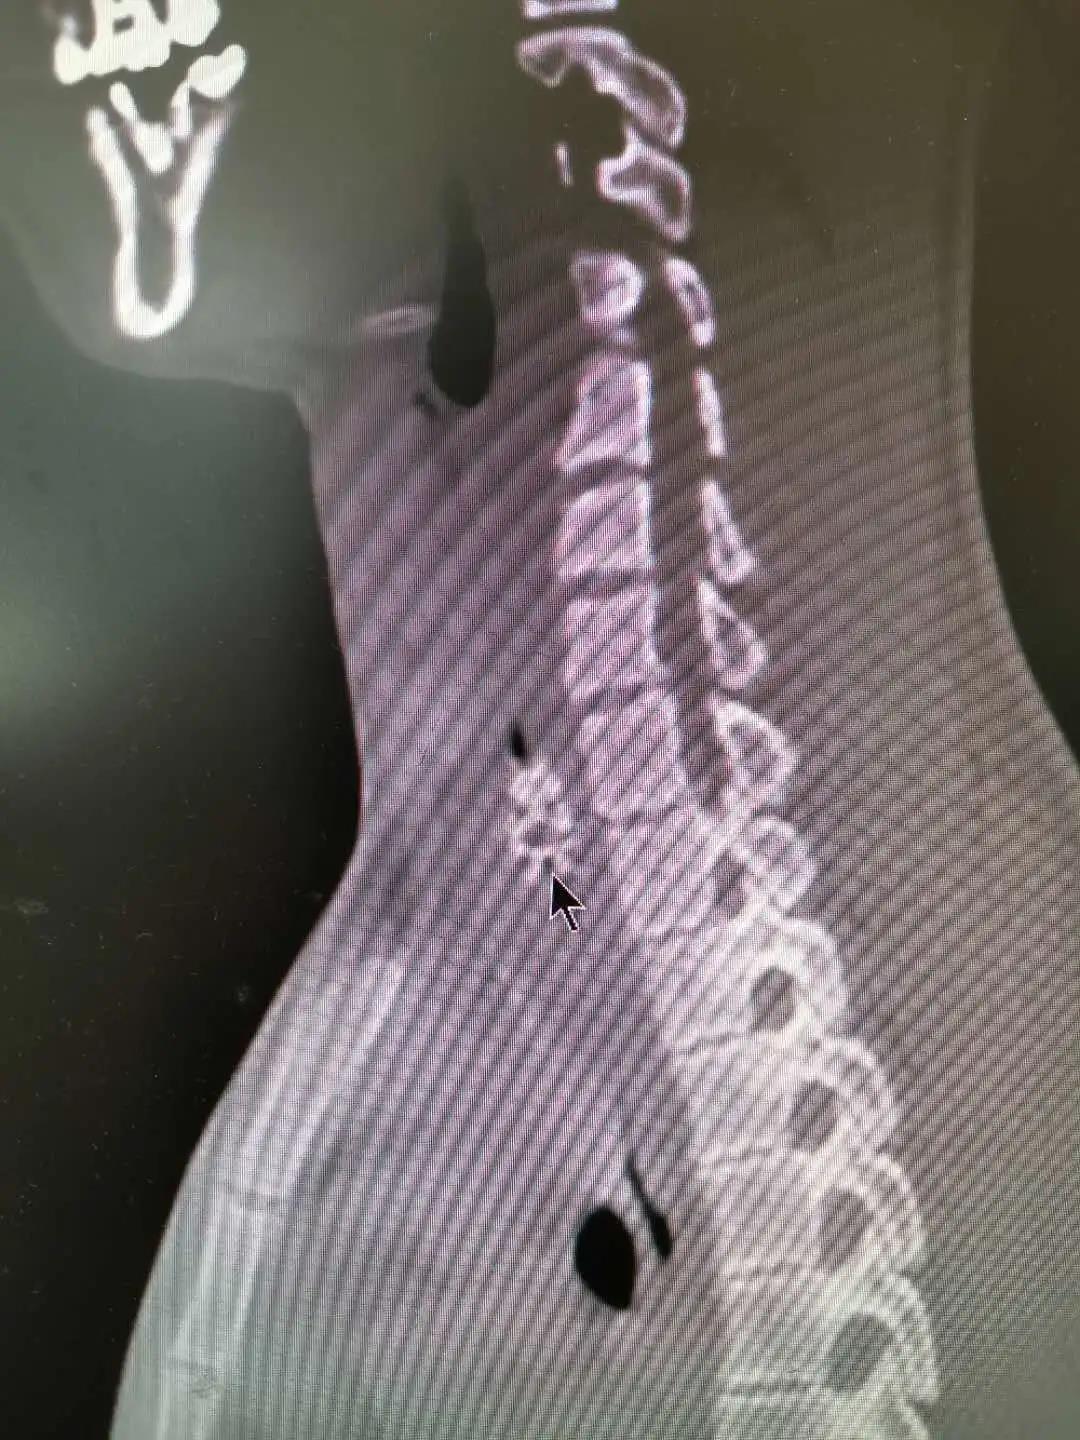

该院耳鼻喉科接诊医生仔细询问病史后怀疑为食管异物,食道CT提示在食管上段处有异物。第二天,小杨被收入耳鼻喉科的住院部,当天下午便接受了食道镜手术治疗。从食道镜检查到内镜取异物,整个过程仅用了10分钟,其中取异物用时仅1分钟,术中没有出血。